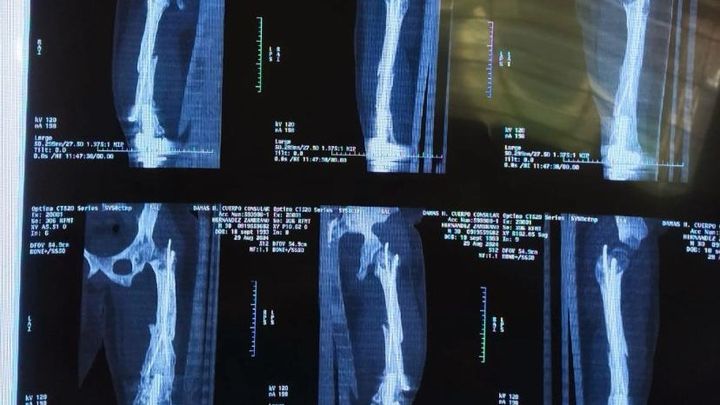

Today we are writing to you with our hearts in our hands to ask for your support in a difficult time for our family. Our son Tito was born with a medical condition known as hypoplasia of the right femur, for which he has required multiple surgeries since he was a baby, until now. Two years ago, he received a knee prosthesis that allowed him to significantly improve, reducing his shortening to just 1 cm.

However, in December 2023, Tito suffered a fracture in his femur, and intramedullary nails were placed to try to stabilize the bone. Unfortunately, the bone is not consolidating and he needs urgent further surgery to correct this complication and allow him to lead a normal, pain-free life.